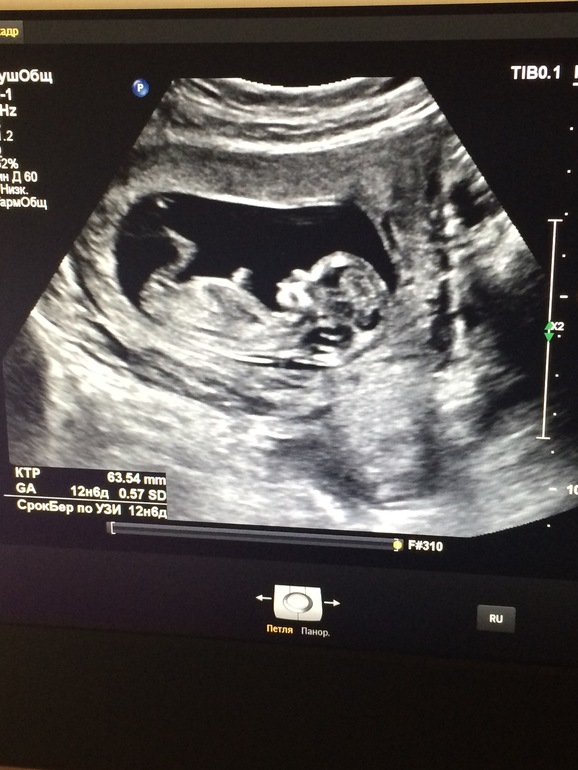

Начали мы в марте, и закончили тоже, так как в апреле я поняла. что беременна)

Сейчас я на 23,4 неделе беременности, ждём мальчишку)